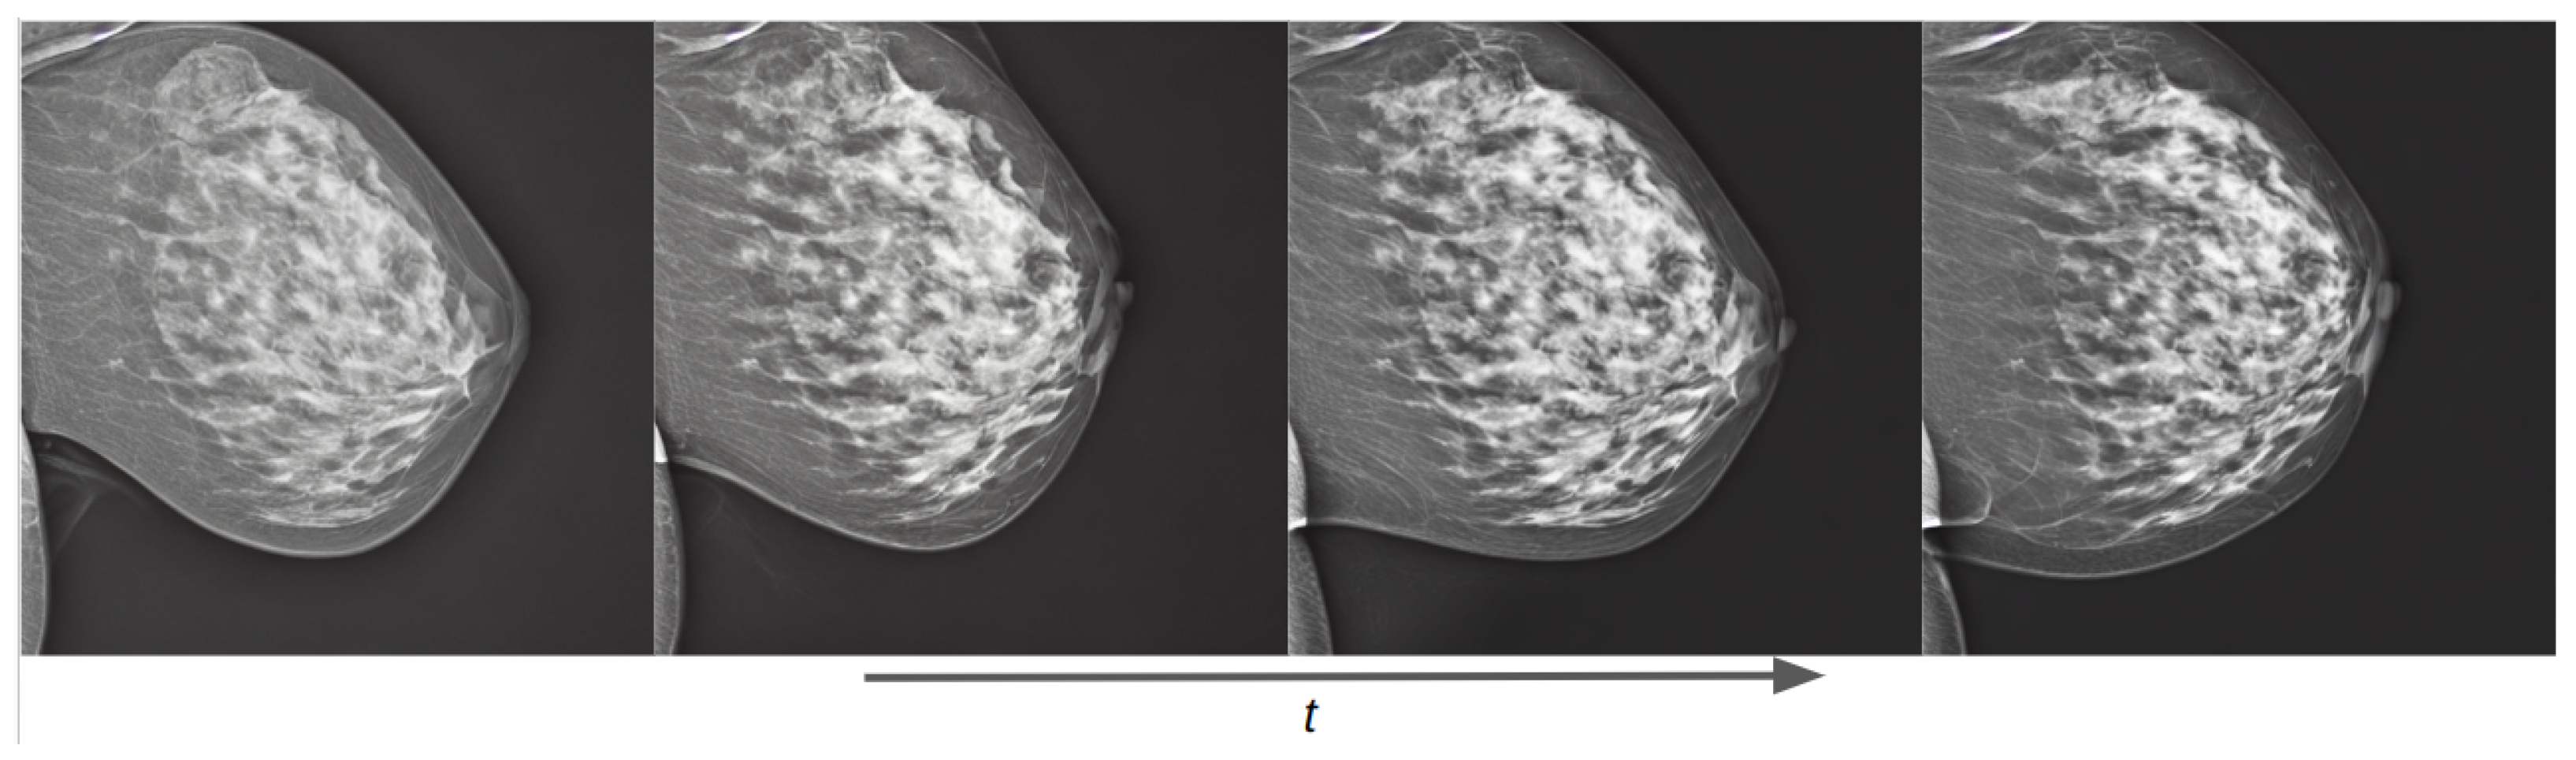

3.2. Lesion Generation